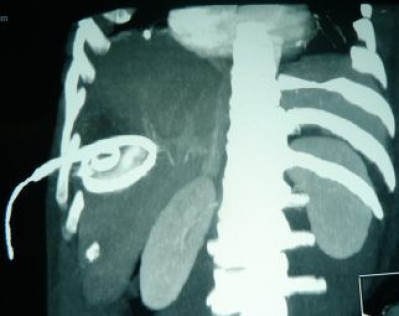

Drenaje percutáneo de absceso hepático

Envíado por Dr. Carlos Miguel Zavaleta Consuegra